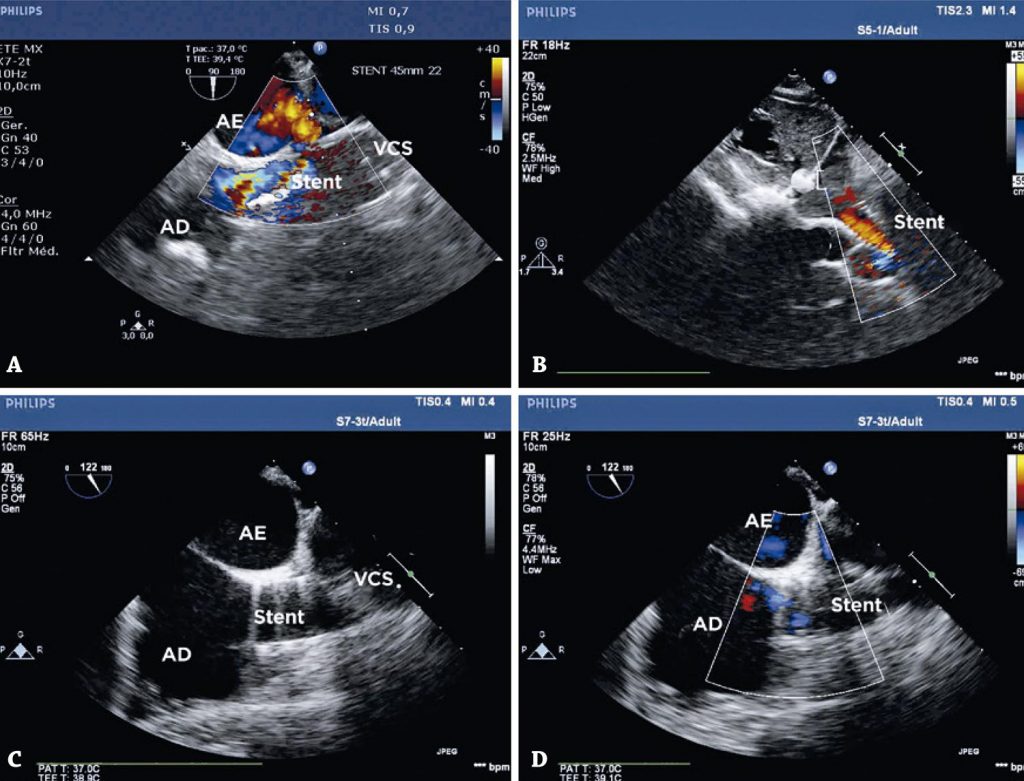

Todos os pacientes foram selecionados por imagens de ecocardiograma transesofágico e, após consentimento livre e informado, foram encaminhados para uma tentativa de oclusão transcateter. Os procedimentos foram realizados sob anestesia geral e intubação orotraqueal. Os traçados de pressão foram obtidos por cateterismo das câmaras direita e esquerda. Foram realizadas angiografias de contraste seletivo na veia cava superior e na veia pulmonar superior direita. A angiografia seletiva simultânea da veia pulmonar superior direita foi obtida após a oclusão da veia cava superior com balões de maior tamanho. Os pacientes que apresentaram persistência do fluxo da veia pulmonar para o átrio esquerdo, apesar da oclusão da veia cava superior, foram submetidos ao fechamento da comunicação interatrial do tipo seio venoso por meio de stents cobertos, implantados na veia cava superior para corrigir o defeito.

Quatro pacientes (dois homens) foram selecionados para procedimentos de oclusão. A idade variou de 30 a 53 anos. O implante foi possível em 50% dos pacientes. No restante, a oclusão da veia cava superior mostrou interrupção do fluxo da veia pulmonar superior direita nesse nível. O procedimento foi interrompido, e os pacientes foram encaminhados eletivamente para cirurgia. Não houve shunts residuais nos pacientes tratados, nem complicações relacionadas ao procedimento.